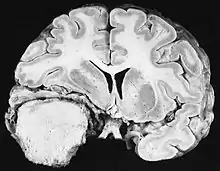

Up to 10% of invasive cancers are related to radiation exposure, including both non-ionizing radiation and ionizing radiation.[8] Unlike chemical or physical triggers for cancer, ionizing radiation hits molecules within cells randomly. If it happens to strike a chromosome, it can break the chromosome, result in an abnormal number of chromosomes, inactivate one or more genes in the part of the chromosome that it hit, delete parts of the DNA sequence, cause chromosome translocations, or cause other types of chromosome abnormalities.[65] Major damage normally results in the cell dying, but smaller damage may leave a stable, partly functional cell that may be capable of proliferating and developing into cancer, especially if tumor suppressor genes were damaged by the radiation.[65] Three independent stages appear to be involved in the creation of cancer with ionizing radiation: morphological changes to the cell, acquiring cellular immortality (losing normal, life-limiting cell regulatory processes), and adaptations that favor formation of a tumor.[65] Even if the radiation particle does not strike the DNA directly, it triggers responses from cells that indirectly increase the likelihood of mutations.[65]

Ionizing radiation

Sources of ionizing radiation include medical imaging, and radon gas. Ionizing radiation is not a particularly strong mutagen.[65] Medical use of ionizing radiation is a growing source of radiation-induced cancers. Ionizing radiation may be used to treat other cancers, but this may, in some cases, induce a second form of cancer.[65] Radiation can cause cancer in most parts of the body, in all animals, and at any age, although radiation-induced solid tumors usually take 10–15 years, and can take up to 40 years, to become clinically manifest, and radiation-induced leukemias typically require 2–10 years to appear.[65] Radiation-induced meningiomas are an uncommon complication of cranial irradiation.[70] Some people, such as those with nevoid basal cell carcinoma syndrome or retinoblastoma, are more susceptible than average to developing cancer from radiation exposure.[65] Children and adolescents are twice as likely to develop radiation-induced leukemia as adults; radiation exposure before birth has ten times the effect.[65]

Ionizing radiation is also used in some kinds of medical imaging. In industrialized countries, medical imaging contributes almost as much radiation dose to the public as natural background radiation. Nuclear medicine techniques involve the injection of radioactive pharmaceuticals directly into the bloodstream. Radiotherapy deliberately deliver high doses of radiation to tumors and surrounding tissues as a form of disease treatment. It is estimated that 0.4% of cancers in 2007 in the United States are due to CTs performed in the past and that this may increase to as high as 1.5–2% with rates of CT usage during this same time period.[71]

Residential exposure to radon gas has similar cancer risks as passive smoking.[65] Low-dose exposures, such as living near a nuclear power plant, are generally believed to have no or very little effect on cancer development.[65] Radiation is a more potent source of cancer when it is combined with other cancer-causing agents, such as radon gas exposure plus smoking tobacco.[65]